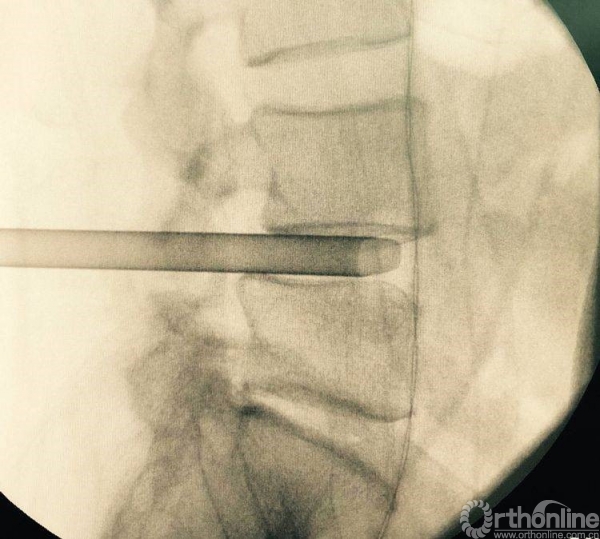

处理干净椎间隙后,透视观察工作通道的位置,镜下看到前纵韧带的纤维交错位置,为减压充分标志

正位观察透视,判断是否处理至边缘

充分植骨(关节成型时的自体骨质、也可配合异体骨使用),然后植入融合器,镜下观察融合器和硬膜囊位置并透视再次确认

正侧位透视观察滑脱是否复位、融合器及植骨的位置

镜下观察有无碎骨块,融合器与硬膜囊位置关系